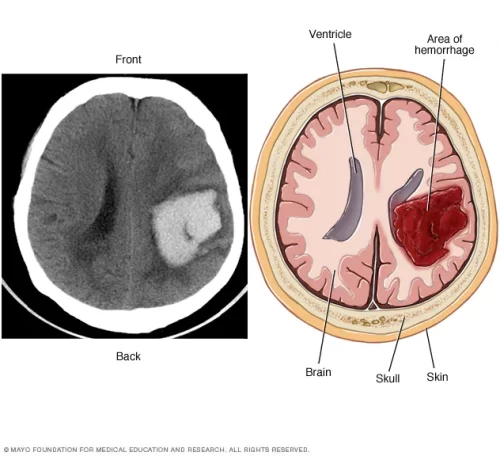

- ๐ฉป Non-contrast CT: gold standard

- Quantify volume (mGS โฅ5 โ poor prognosis)

- Assess parenchymal component, mass effect, hydrocephalus

- Signs: โCastโ (ventricles filled), โSwirlโ (active bleeding)